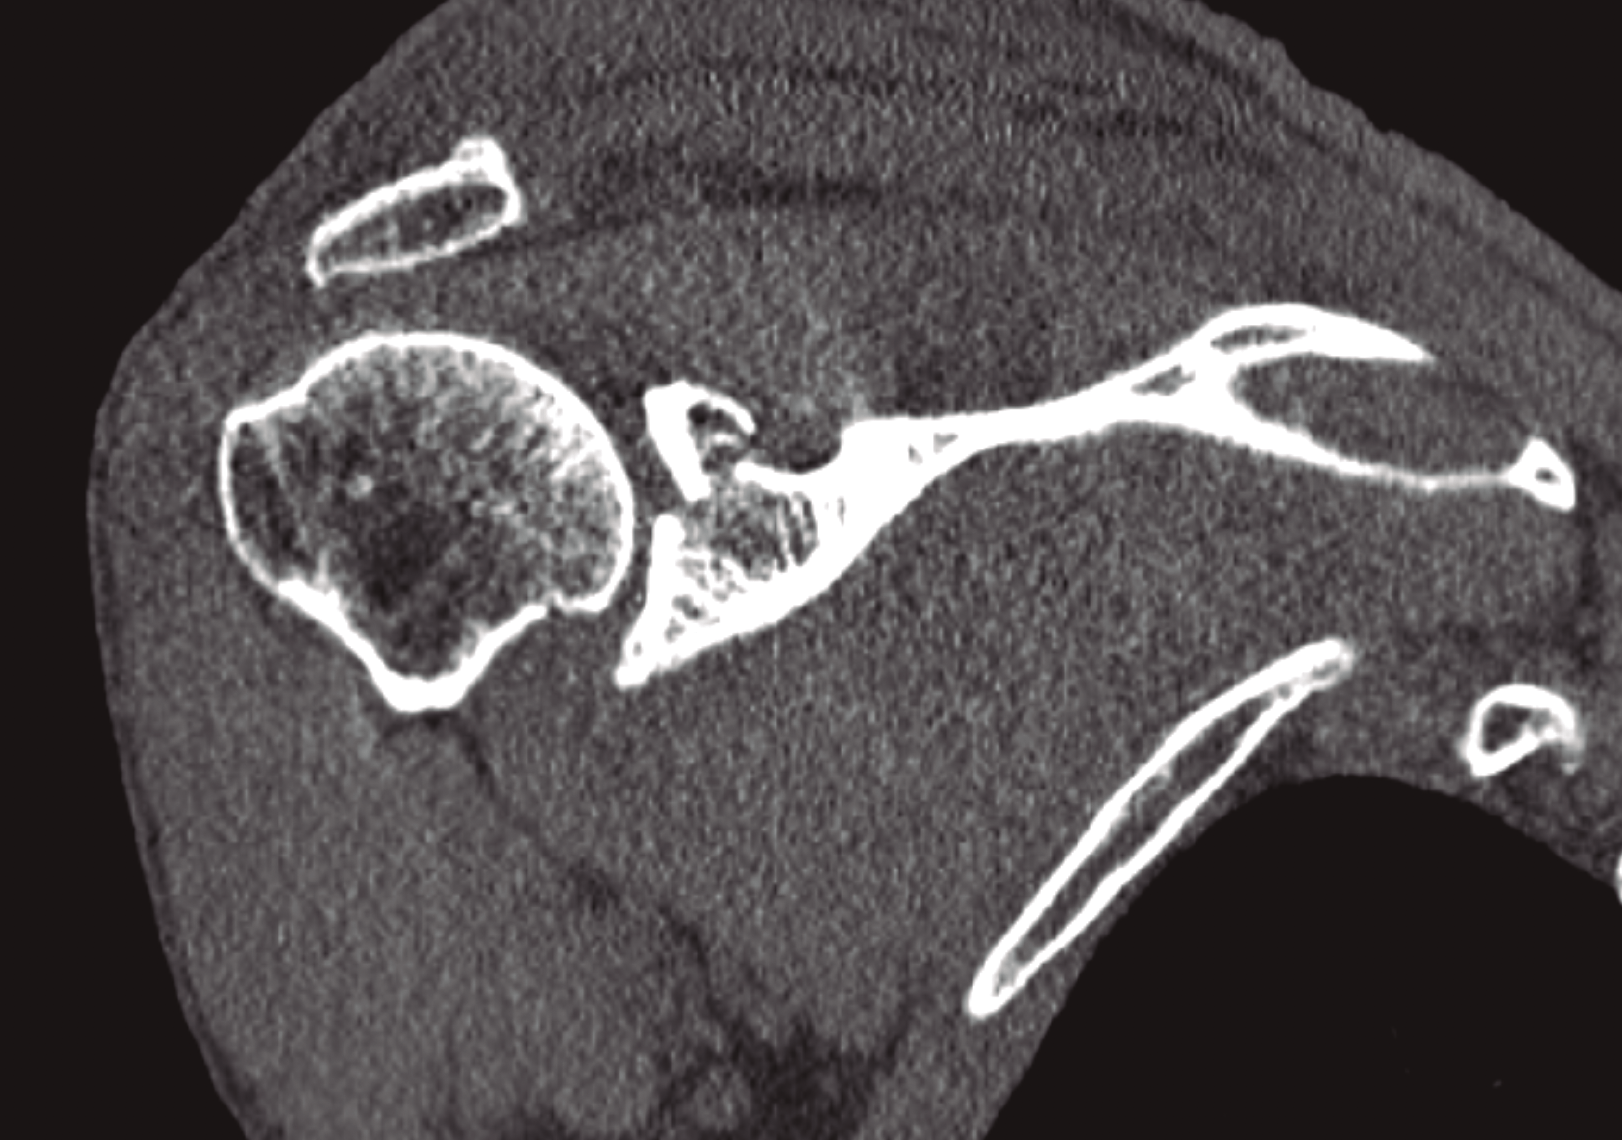

Completamos el estudio con una tomografía computarizada (TC) que nos informa de fractura conminuta del acromion con leve desplazamiento y fractura de la cavidad glenoidea con trazo transverso supraglenoideo que incluye la apófisis coracoides, con desplazamiento de los fragmentos mayor de 1 cm y que supone un escalón articular de 3,5 mm (Figura 2).

Figura 2. Obsérvese el importante desplazamiento que presenta la fractura del margen superior de la glena.